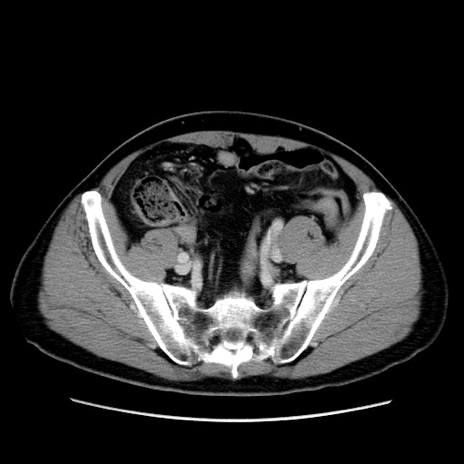

症例34(横断像)

【症例】60歳代 男性

【主訴】右鼠径部膨隆

【現病歴】1年程前より右鼠径部膨隆あり。自己にて還納可能だったため放置していた。3時間前より右鼠径部の脱出を認め、還納困難となり受診。

【既往歴】高血圧

【身体所見】右鼠径部に小児頭大の膨隆あり。弾性硬であり、用手還納は困難。左鼠径部にも膨隆を認める。脱出はなし。

【データ】WBC 15500、CRP 測定なし